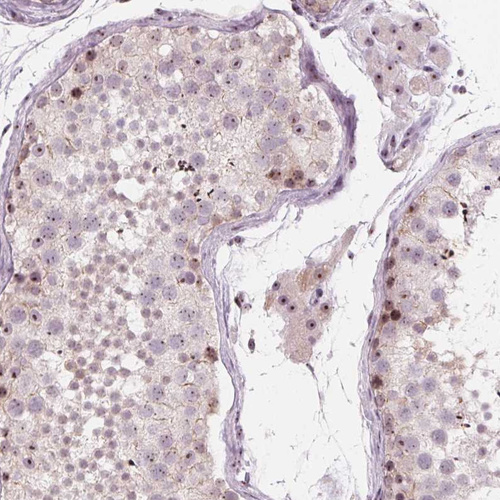

Immunohistochemical staining of human tonsil tissues show strong positivity in nucleoli in germinal center cells and non germinal cells.